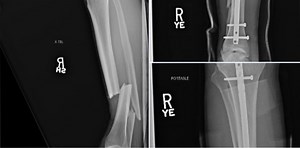

Chris Weidman shares x-ray of broken leg

UFC star Weidman shares horror X-ray pics of broken leg bone with r

Chris Weidman Shares REAL Xrays of Broken Leg from UFC 261 - Doc

Chris Weidman: I Have More Metal Than Bone in Injured Leg at This P

Chris Weidman X-Rays of Leg Injury Revealed | UFC 261 FALLOUT Show